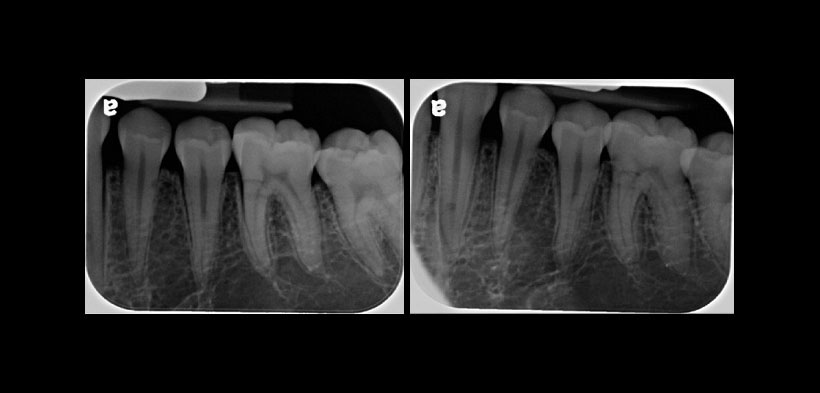

Fig. 1. Radiografía periapical digital de la pieza 3.4. Toma ortogonal (izquierda) y la correspondiente proyección mesioangulada (derecha) de la pieza 3.4 con sospecha de reabsorción radicular externa (RRE).